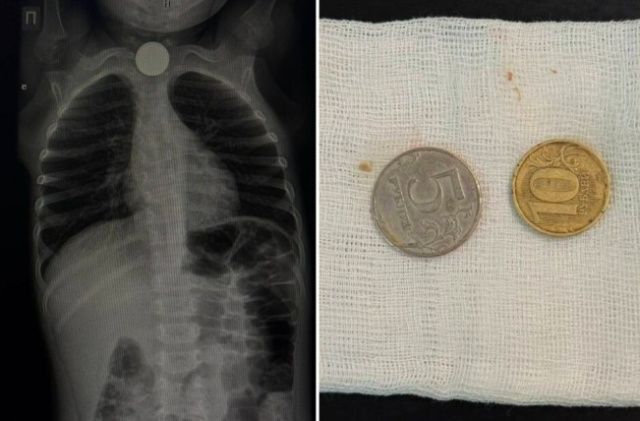

Мальчика беспокоили кашель и обильное слюнотечение. Экстренную операцию провела врач-эндоскопист, заведующая эндоскопическим отделением РБ № 1 – НЦМ Мария Еремеева.

«Родители обратились в больницу в тот же день, когда ребенок проглотил монеты. Инородные тела были обнаружены в верхней трети пищевода. Операция прошла успешно, сложностей при извлечении монет не возникло. После операции ребёнок в удовлетворительном состоянии остался под наблюдением в хирургическом отделении», — рассказала Мария Еремеева.